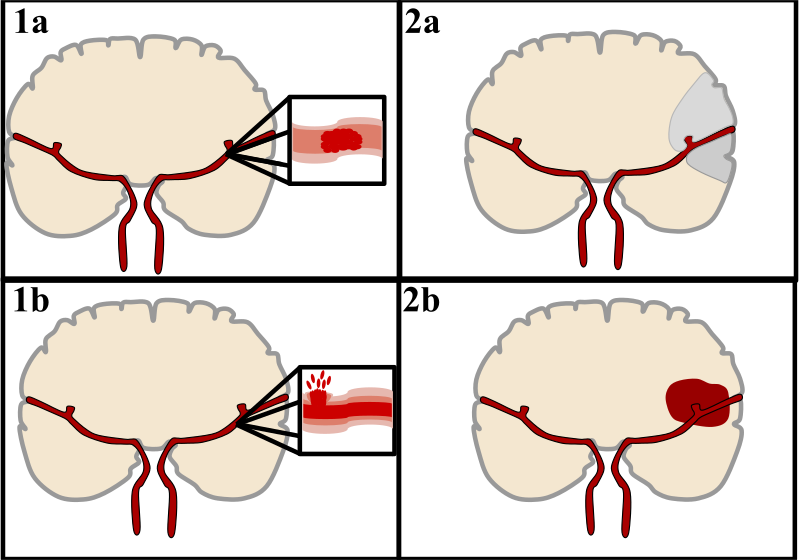

Intracerebral Hemorrhage

An intracerebral hemorrhage is due to brain parenchyma bleeding.

Intracerebral hemorrhage may result from:

- Lenticulostriate vessel rupture

- Aneurysm rupture

The most typical location of the brain involved by intracerebral hemorrhage is the basal ganglia.

Intracerebral hemorrhage hemorrhages may be caused by hypertension.

Hypertension treatment decreases the risk of intracerebral hemorrhage by half.

Subarachnoid Hemorrhage

Subarachnoid hemorrhage is hemorrhage that involves the subarachnoid area of the brain.